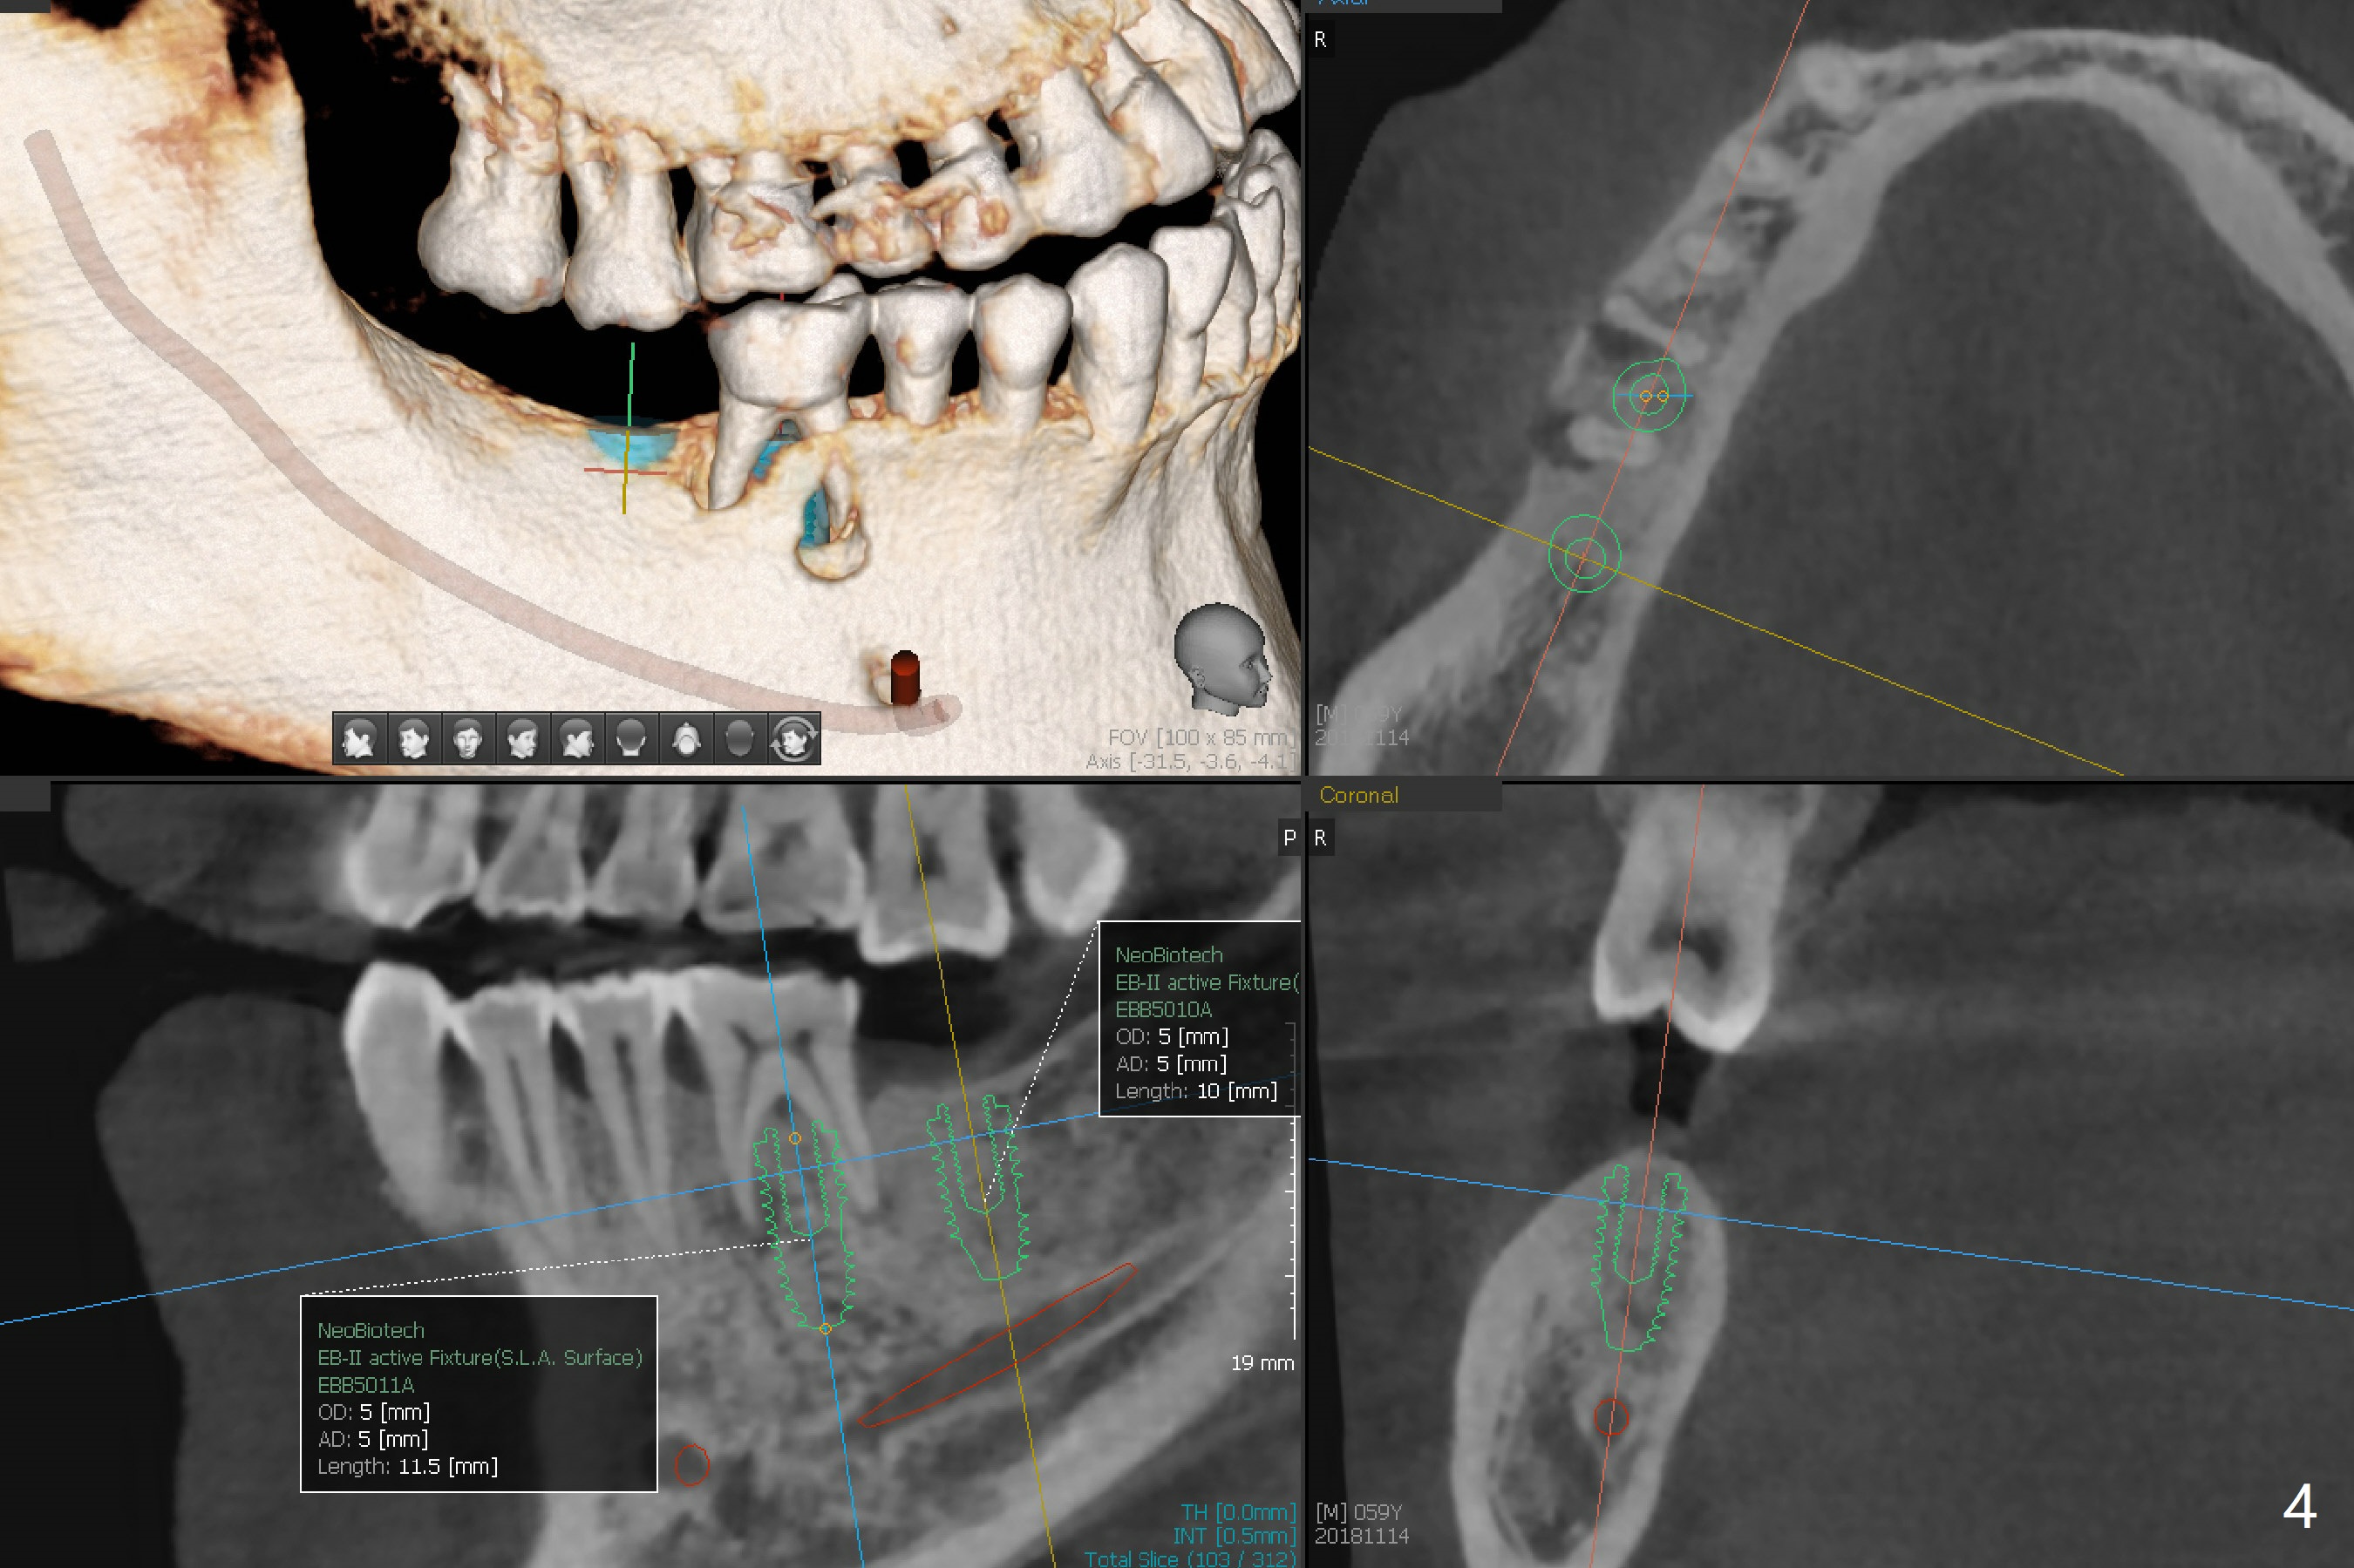

A 59-year-old man has subgingival fracture of the lingual cusps of the tooth #30 (Fig.1) with PARL, especially of the mesial root (Fig.2). An immediate implant will be placed slightly distolingually (Fig.3), while the delayed implant at #31 will be placed in a restorative position (Fig.4). Treat plan orthodontic intrusion of the tooth #2 if the latter is salvageable with periodontal lesion (Fig.1). Keep the tooth #1 in case bands and segmental wire are needed. It will be extracted prior to impression. After extraction, place a bony anchor pin at #31 for #30 osteotomy. When an implant is placed at #30, place a fixture anchor pin and finish osteotomy at #31.